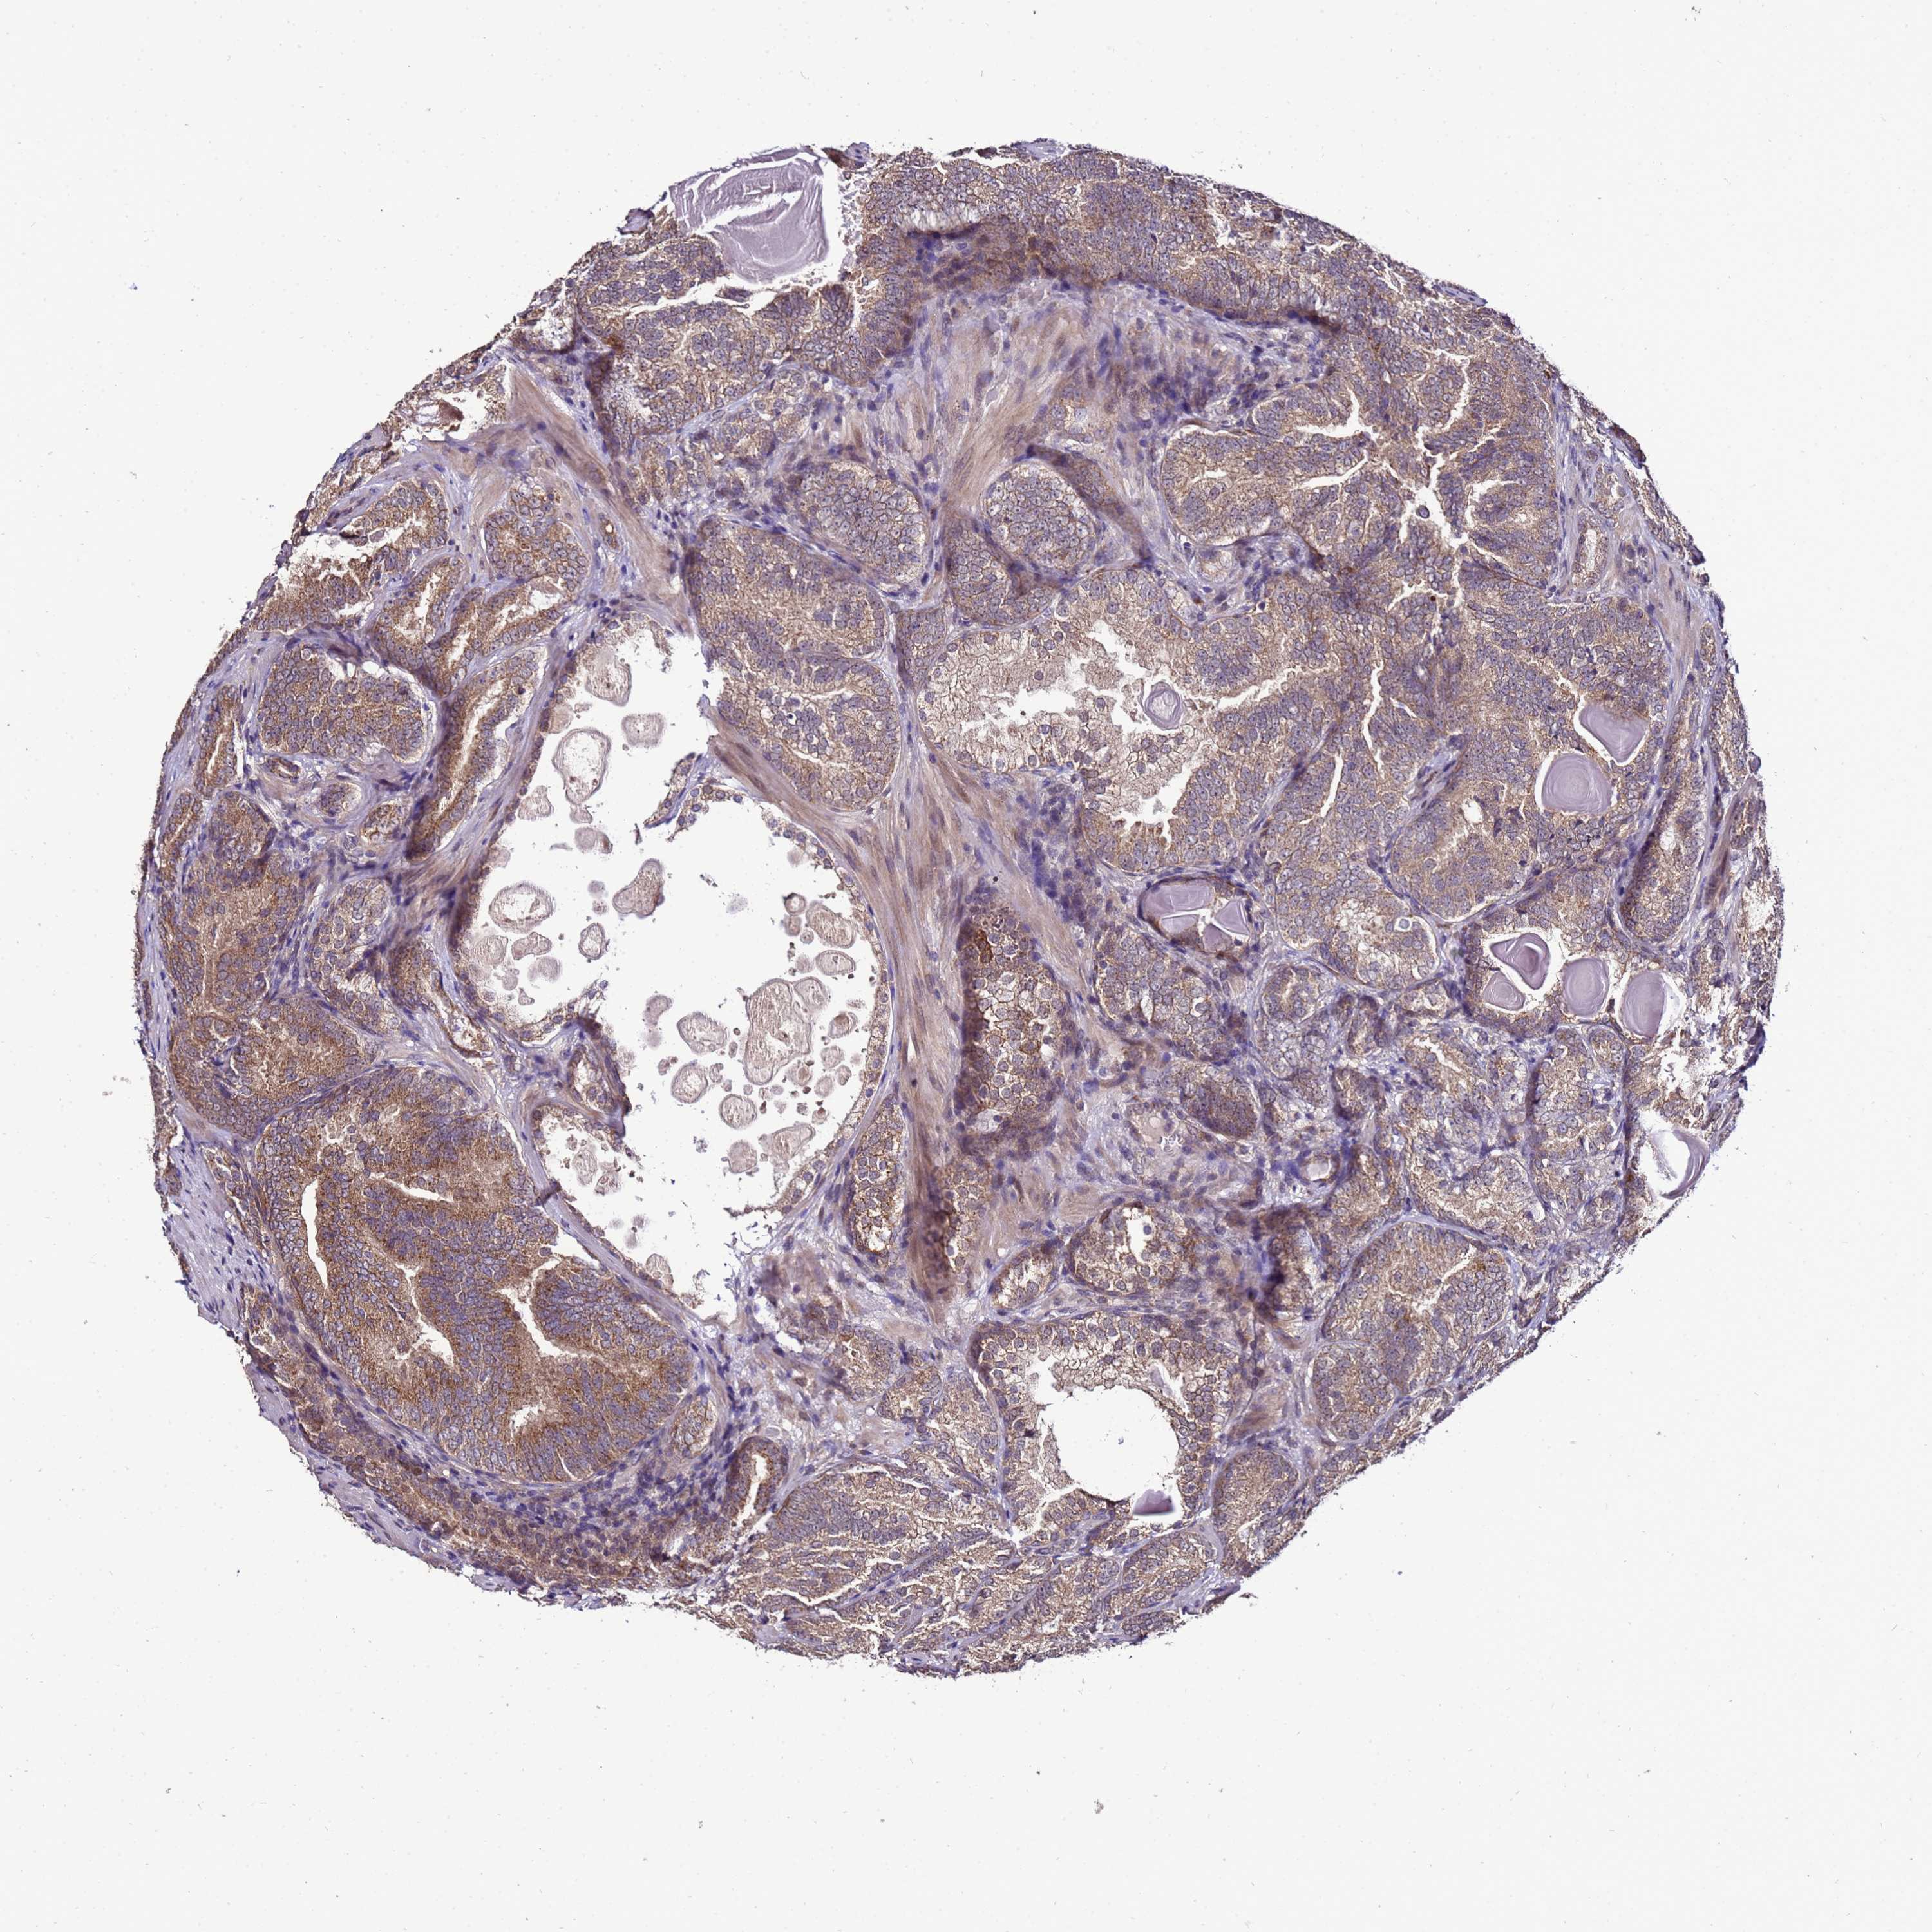

PROSTATE CANCER - Protein expressioni

A mouse-over function shows sample information and annotation data. Click on an image to view it in a full screen mode. Samples can be filtered based on level of antibody staining by selecting one or several of the following categories: high, medium, low and not detected. The assay and annotation is described here.

Note that samples used for immunohistochemistry by the Human Protein Atlas do not correspond to samples in the TCGA dataset.

Antibody stainingi

Antibody staining in the annotated cell types in the current human tissue is reported as not detected, low, medium, or high, based on conventional immunohistochemistry profiling in selected tissues. This score is based on the combination of the staining intensity and fraction of stained cells.

Each image is clickable and will lead to virtual microscopy that enables deeper exploration of all samples and also displays staining intensity scores, fraction scores and subcellular localization as well as patient and tissue information for each sample.

Antibody HPA044373

Staining

High

Medium

Low

Not detected

Intensity

Strong

Moderate

Weak

Negative

Quantity

>75%

75%-25%

<25%

None

Location

Nuclear

Cytoplasmic/membranous

Cytoplasmic/membranous,nuclear

Adenocarcinoma, NOS

Adenocarcinoma, High grade

Adenocarcinoma, Low grade